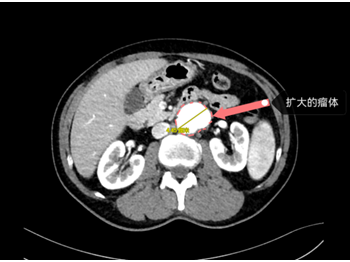

主动脉CT血管造影检查结果是

腹主动脉夹层动脉瘤

直径已达到4.45厘米